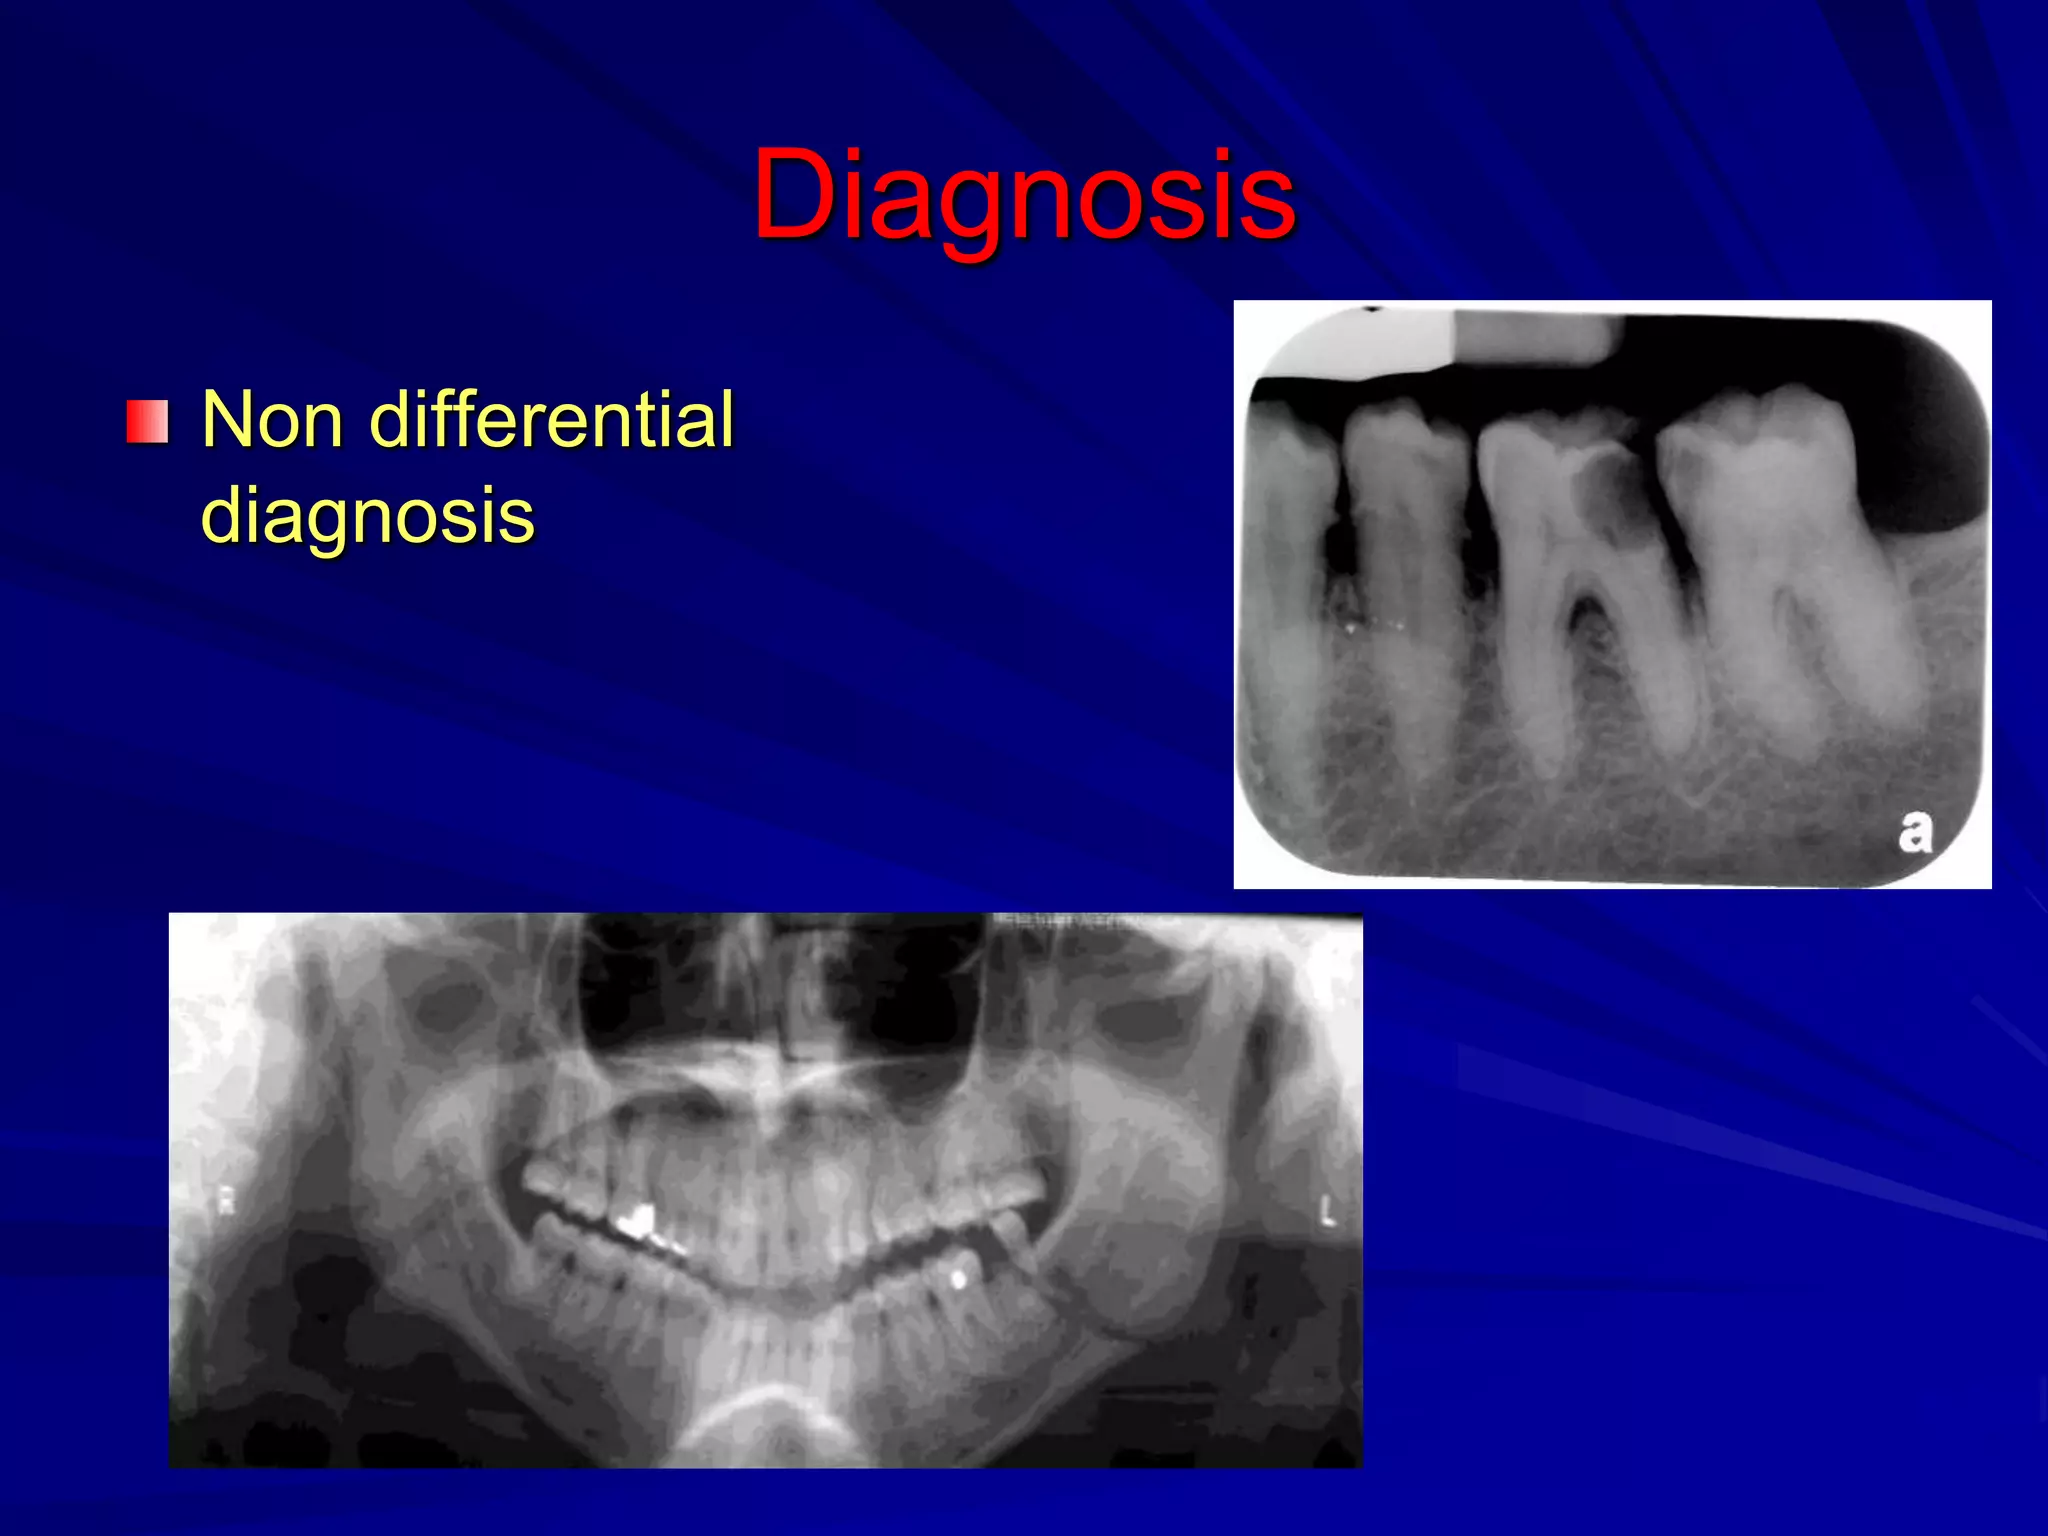

Diagnosis

Non differential diagnosis

Differential diagnosis

Non differential